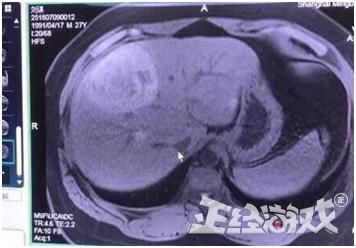

这是MRI图啊朋友.....

仅凭爆料的MRI图,就敢诊断出原发性肝癌......